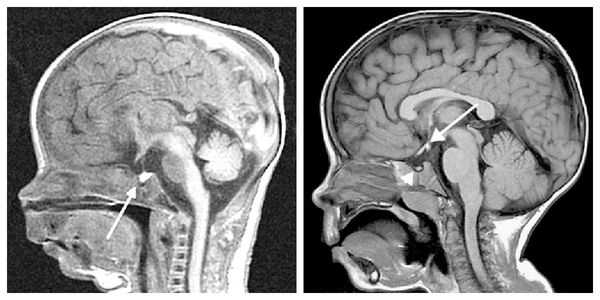

У некоторых пациентов с мутацией конкретных генов выявляется гиперплазия передней доли гипофиза (аденогипофиза). В процессе жизни может произойти её атрофия вплоть до формирования синдрома "пустого турецкого седла" — недостаточности области головного мозга, где расположен гипофиз. Данный синдром приводит к внедрению мягкой мозговой оболочки в полость турецкого седла, сдавлению и уменьшению гипофиза, что нарушает или полностью прекращает его работу.

При необходимости проводится МРТ головного мозга и гипофиза с контрастированием [6] . Она позволяет исключить или подтвердить наличие объёмных образований области гипофиза и головного мозга.